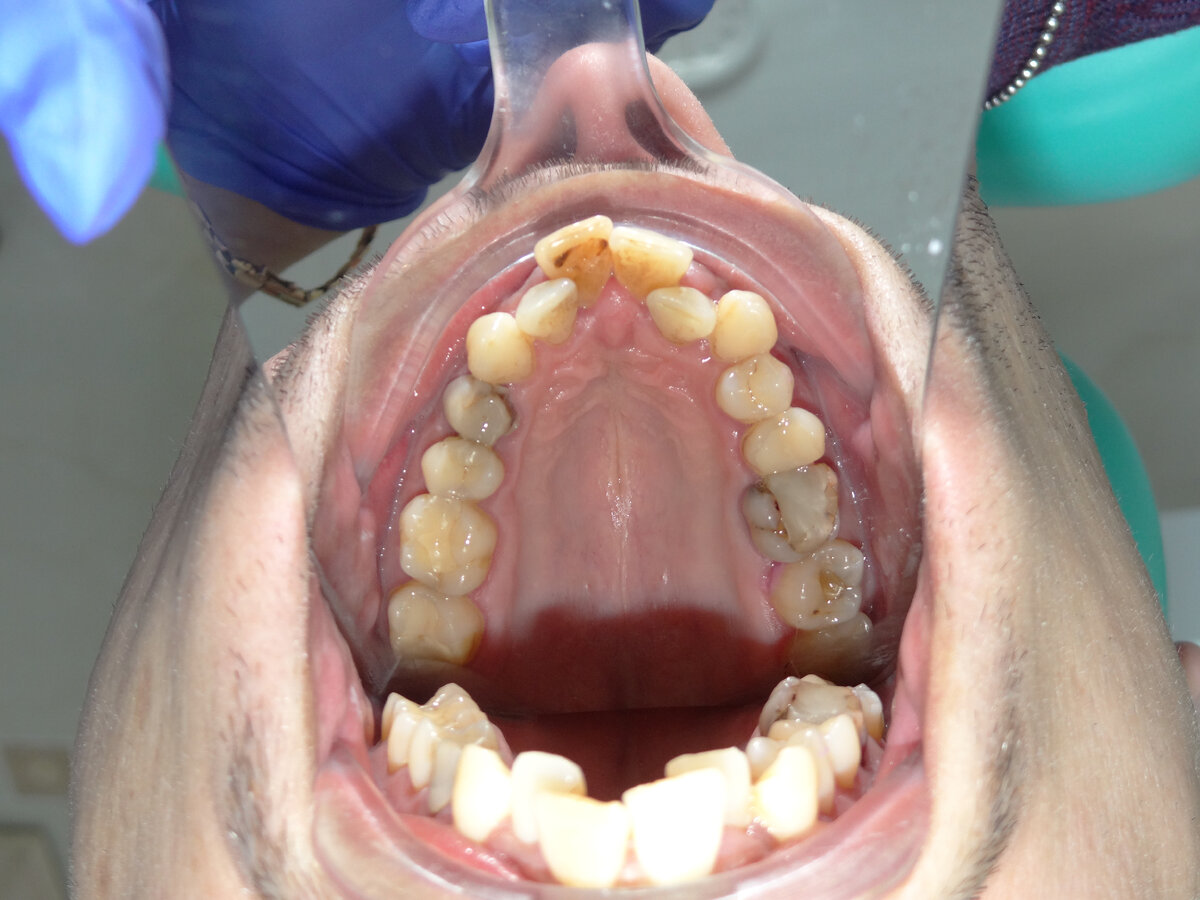

Фото верхней челюсти: частая ортодонтическая  проблема  - это узкая верхняя челюсть. После анализа состояния зубов были выявлены требующие лечения.

1. Провести лечение всех зубов( лечение кариеса и корневых каналов);

2. Ортодонтическое лечение на брекет-системе для расстановки зубов в правильные позиции

3. Установка имплантатов в зону отсутствующих зубов

4. Установка виниров на передние зубы и коронок на имплантаты

На первом этапе мы начали лечить кариозные зубы и корневые каналы. Часто у нас спрашивают, почему нельзя сразу поставить брекеты? Зачем лечить зубы?